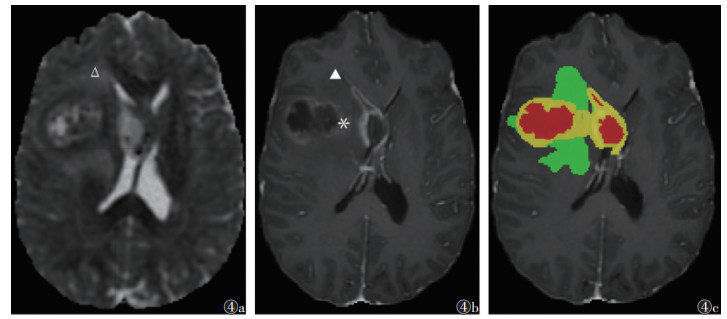

| 注:患者,女,58岁,IDH野生型胶质母细胞瘤;图4a为RD图,可见瘤周水肿远侧区域呈稍高信号(Δ);图4b,4c分别为T1WI增强扫描图像、分割图像,可见肿瘤强化范围较大(图4b*,图4c黄色区域),瘤周水肿范围较小(图4b▲,图4c绿色区域),即体积比强化/水肿大 图 4 胶质母细胞瘤异柠檬酸脱氢酶(IDH)野生型的体积比强化/水肿及径向扩散率(RD)图 |

ROC曲线显示,AUC及约登指数最高的参数分别为FA水肿近侧、体积比强化/水肿、RD水肿近侧、RD水肿远侧、MD水肿远侧,其敏感度分别为0.750、0.909、0.800、0.900、0.850,特异度分别为0.779、0.571、0.634、0.572、0.579(表 2)。对上述参数进行联合诊断,联合诊断预测因子=exp(-2.398×体积比强化/水肿-14.017×FA水肿近侧-4.648×MD水肿远侧+1.890×RD水肿近侧+7.482×RD水肿远侧-3.770),当截断值为0.162时,敏感度为0.800,特异度为0.826,约登指数为0.626,AUC为0.866,诊断效能优于各参数单独诊断(图 2)。对上述参数进行串联及并联试验,结果表明,各参数串联试验诊断效能均有提升,RD水肿远侧与体积比强化/水肿这一组合的约登指数最高,其次分别是MD水肿远侧与体积比强化/水肿、FA水肿近侧与体积比强化/水肿、MD水肿远侧与RD水肿远侧、RD水肿远侧与FA水肿近侧(表 3)。体积比强化/水肿小而RD水肿远侧高为IDH突变的可能更高(图 3,4)。

此外,动态磁敏感对比增强灌注加权成像(dynamic susceptibility contrast-perfusion weighted imaging,DSC-PWI)也被用于鉴别HGG的IDH突变状态,其关键指标为相对脑血容量(relative cerebral blood volume,rCBV)。Pons-Escoda等[24]发现,rCBV对HGG的IDH突变状态的诊断效能较高(AUC=0.811)。Xing等[25]利用rADC与rCBV联合预测HGG的IDH突变情况,进一步提高了诊断效能(AUC=0.895)。本研究联合诊断包含了5个参数,临床应用存在一定不便。本研究通过串联试验(降低了净敏感度,但提升了净特异度)确定了兼具敏感度和特异度的诊断性指标组合,RD水肿远侧与体积比强化/水肿联合约登指数最高,表明水肿远侧区域垂直方向的水分子扩散活动越强,强化区域相对水肿区域比例越小,则越倾向于诊断为IDH突变的HGG。这符合Ⅳ级的星形细胞瘤较胶质母细胞瘤更不易侵袭性生长的特点,肿瘤细胞沿神经纤维的浸润性生长,使水分子的径向扩散受到影响。既往研究报道,HGG瘤周水肿体积相对较小常与IDH突变相关,由于IDH野生型HGG的凝血途径激活和血管内血栓形成导致肿瘤过度缺氧,表现为较多坏死成分和非强化区域[26]。推测上述参数联合可反映胶质瘤细胞沿神经纤维浸润情况,以及通过反映细胞代谢状态来推断分子表型。